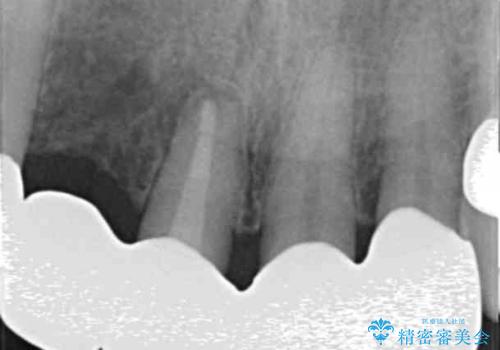

- 前歯の痛み・排膿・ぐらつきの改善を求めて来院されました。

視診・X線写真検査より根尖性歯周炎が認められ再治療が必要な状態です。

再根管治療を行うべくクラウン除去を行ったところ、右上側切歯に保存不可能な垂直性の破折が認められたため抜去が必要になりました。

即切歯の抜歯を行う場合犬歯を含めたブリッジによる補綴計画を立てることが多いですが、今回は犬歯から大臼歯にかかる大きなブリッジが既に装着されていたため予算とご希望を相談し前歯のみの延長ブリッジ補綴で治療を行っていくこととしました。